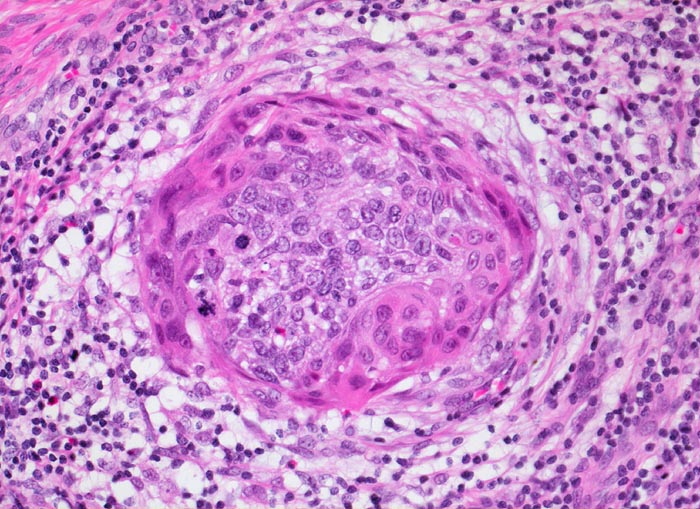

Mikroinvasives Plattenepithelkarzinom der Zervix

Invasiver Herd im Zervixstroma umgeben von desmoplastischer Stromareaktion und Entzündungsinfiltrat.

PAP V, HPV high risk Typen

Histologie

200